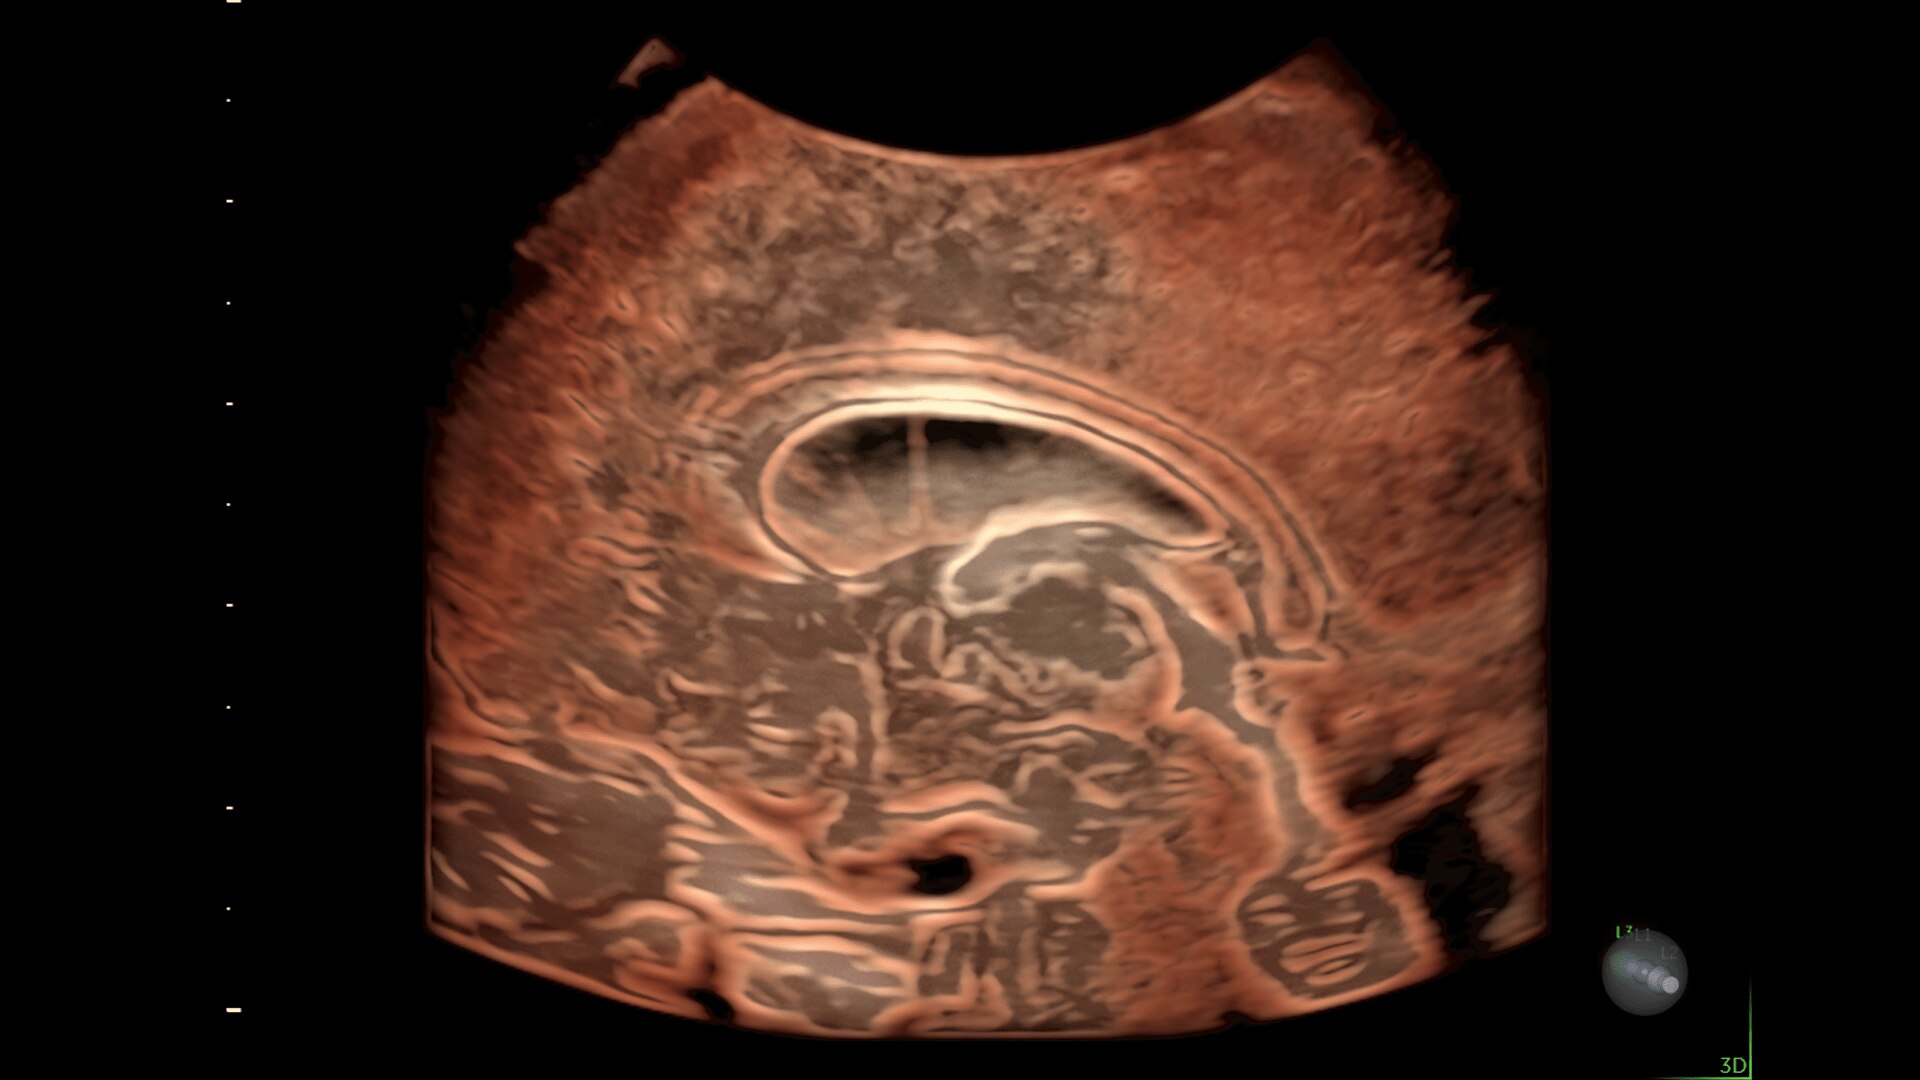

Enhanced Volume Imaging

Deliver next generation 3D/4D & Color images with HDlive Studio+

Super Fine Details

Obtain highly detailed images of the fetal brain, first trimester development, and other complex anatomy with increased axial and lateral resolution.